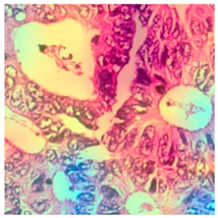

2.4. Model Interpretability

3.6. Visualizing Interpretability in CRC Classification Using ADFMs

| Tissue Class | Original Image | Heatmaps | Superimposed Image |

|  |  |  |

|  |  |  |

|  |  |  |

|  |  |  |